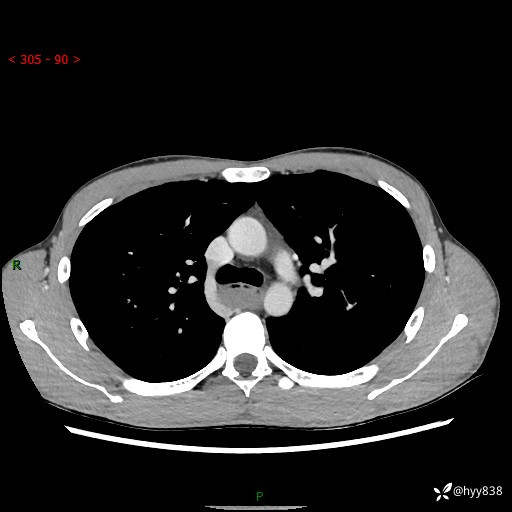

年轻男性,发现后纵隔占位1周余。征象简单,难在定位---结果公布~

现病史:患者于1周前体检行检查发现后纵隔占位,患者平素无明显咳嗽咳痰,无心慌、胸闷、胸痛、呼吸困难、低热、盗汗,无头痛、头晕,无腹痛、腹胀等不适。现患者欲求进一步治疗,遂来我院就诊,以“纵隔占位”收入我科。 患者自起病以来,精神可,睡眠可,饮食可,大小便正常,体重无明显改变。

胸部CT平扫+增强